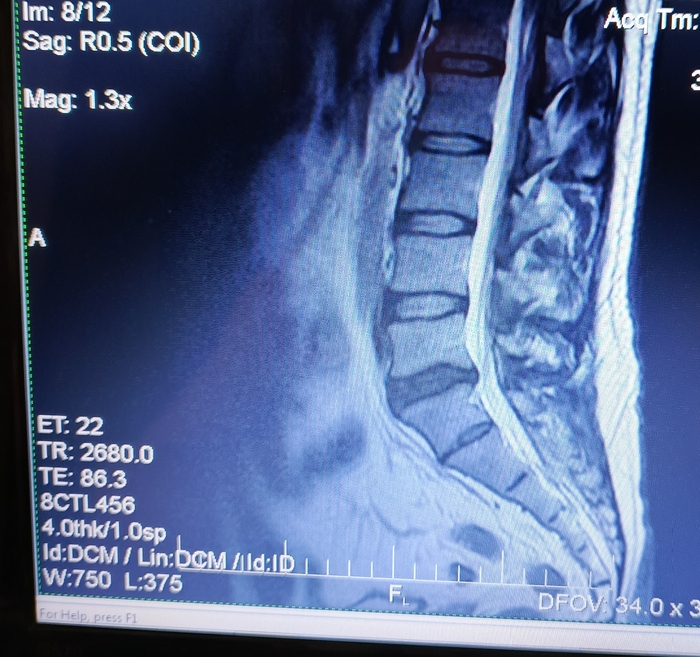

Есть боли в ПОП, в 2020 году на основании МРТ был поставлен диагноз: "Грыжа диска L5/S1. Протрузия диска L4/5."

В 2024 году во время очередного обострения делал повторно МРТ. Диагноз: "Грыжа диска L5/S1. Протрузия диска L4/5. При сравнении с данными 2020 года динамика отрицательная."

2025 год. После очередного обострения и стандартного лечения острая боль прошла, но остались тупые тянущие боли. На днях сделал повторно МРТ. Диагноз: умеренный остеохондроз, с поражением диска L5/S1 с диффузно медианной протрузией.

Собственно вопрос, к тем кто разбирается, действительно ли на данных снимках нет грыжи?

Снимки (с экрана) ниже. Откликнувшихся заранее благодарю.